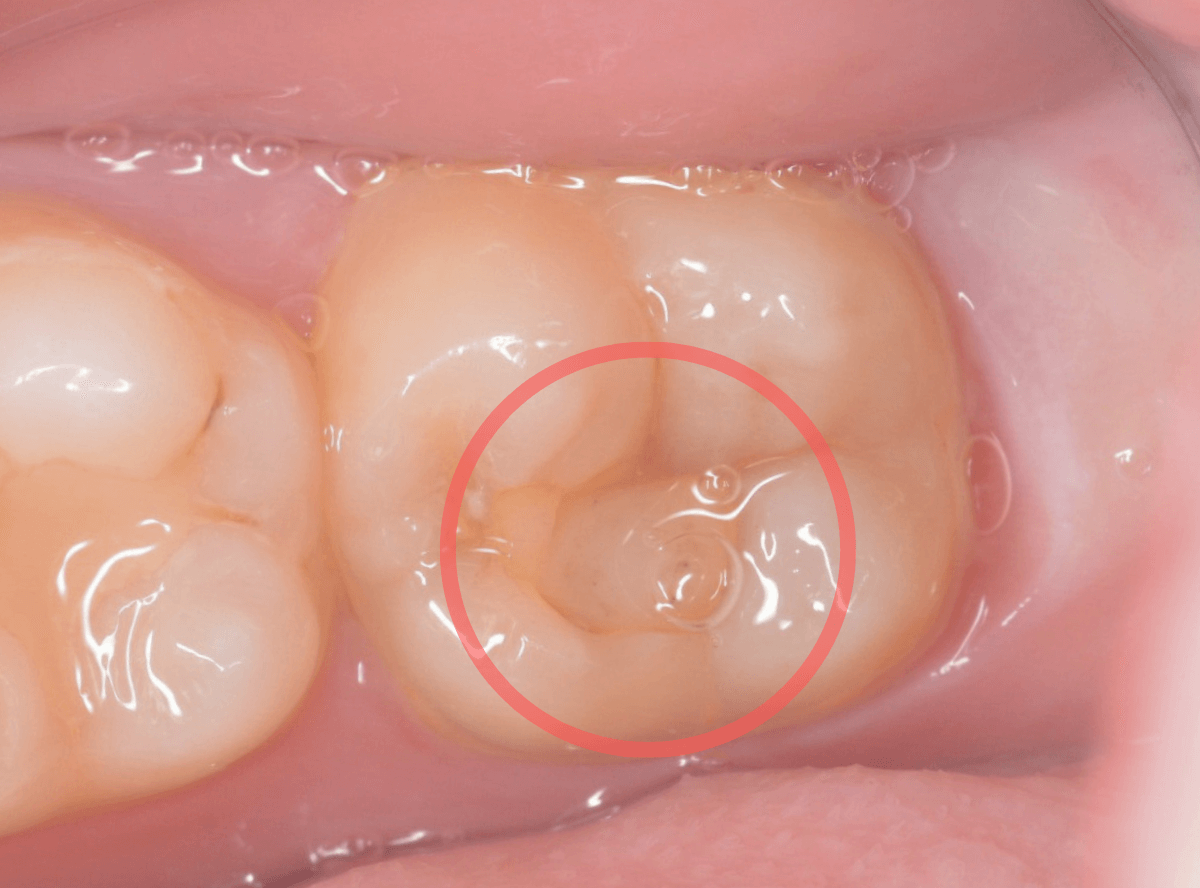

Case.13 問題なさそうなレジンの下で深い虫歯

他の歯の治療希望で来院された患者さんで、レントゲンで大きな虫歯が見つかった方です。

以前に虫歯を削って、レジンをつめる治療がしてあります。

表面を見る限り、特に問題はなさそうです。

レントゲン写真を撮影しました。

青い線が神経

黄色い線がレジン

赤い線が虫歯

です。

思ったよりも深い虫歯をレジンで埋めてあったようで、さらにその中が虫歯になっている状況です。

神経までかなり近い虫歯と思われます。

症状はありません。